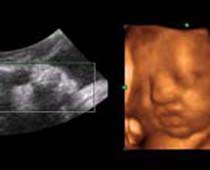

Clips vidéo 4D scan ultrason fœtal | Dr N Layyous

Clips vidéo 4D scan ultrason fœtal